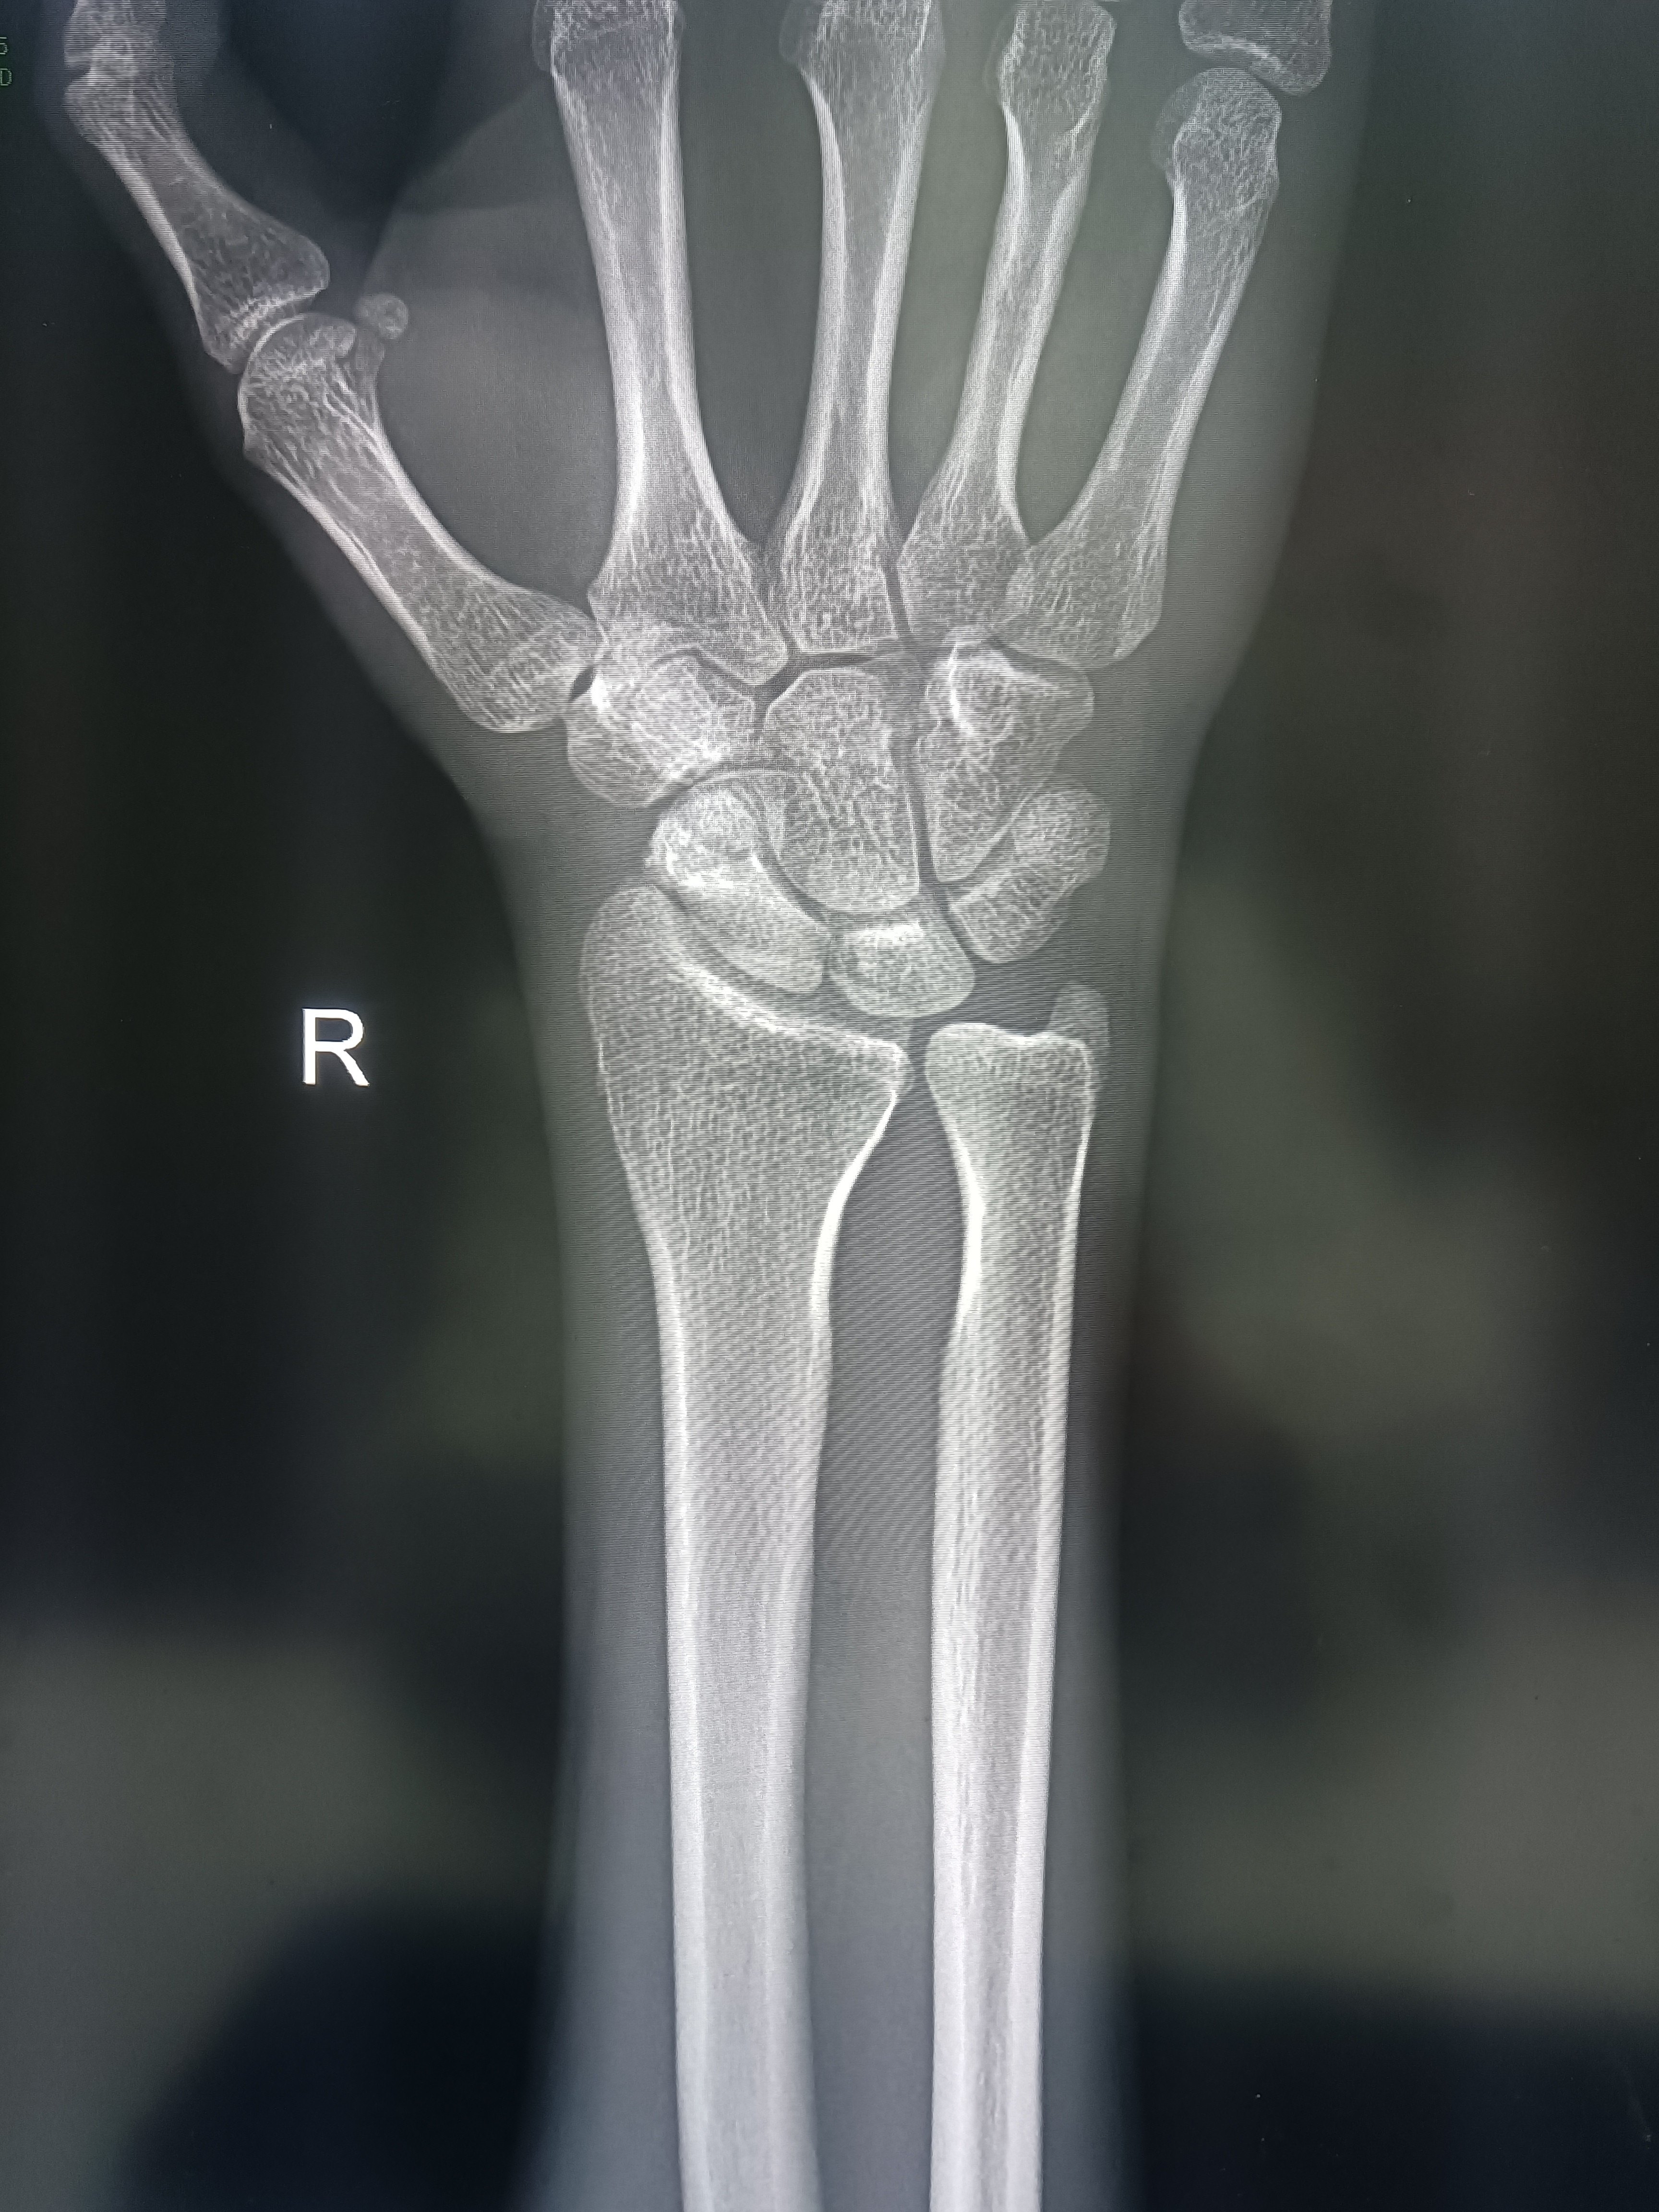

手腕部外伤,请观察一下有无骨折?

请观察手舟骨